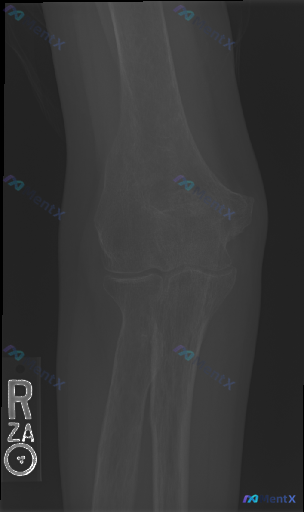

整理到一张右肘部正位的影像资料,先不说是在什么临床背景下拍的。 单纯从这张正位片来看: - 肱骨远端、尺桡骨近端骨皮质连续性看起来还行,关节对合也没明显问题 - 没看到明确的骨折线、脱位,也没明显的骨质破坏、骨赘或者软组织肿胀 但如果告诉你这张片可能是外伤后拍的,而且患者还有肘部疼痛/压痛,会不会觉...